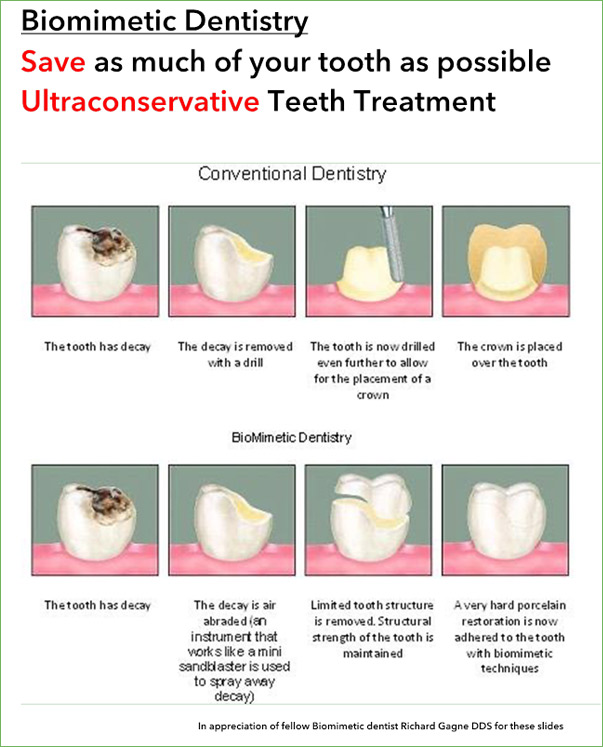

Biomimetics | Free Full-Text | Biomimetic Aspects of Restorative

The Protocols of Biomimetic Restorative Dentistry: 2002 to 2017

The Protocols of Biomimetic Restorative Dentistry: 2002 to 2017

The biomimetically driven restorative dental practice | Dental